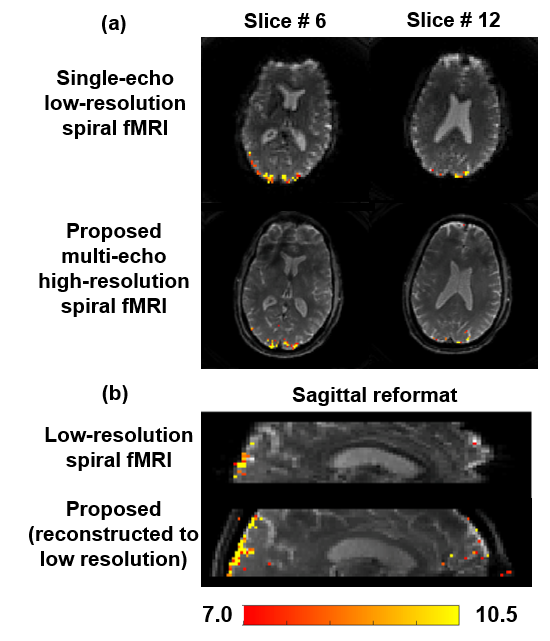

Refer to caption

Fig. 3: Comparison of BOLD sensitivity of single-echo low-resolution spiral fMRI and R=10absent10=10= 10 multi-echo high-resolution spiral fMRI reconstructed with non-Cartesian SSDU. (a) Axial slices show well-preserved activation patterns with the proposed approach, albeit having a 4.7-fold lower baseline SNR compared to the low-resolution acquisition. (b) Sagittal reformats, where the proposed method was reconstructed to the lower resolution, show reliable activation patterns and extent with respect to the baseline low-resolution acquisitions.

Figure 3 shows comparison of BOLD sensitivity analysis, overlaid on images from single-echo low-resolution spiral fMRI and the proposed R=10absent10=10= 10 multi-echo high-resolution spiral fMRI reconstructed using non-Cartesian SSDU. Figure 3a shows comparisons in axial slices. Note that multi-echo high-resolution spiral fMRI has improved in-plane resolution (2 × 2 mm22{}^{2}start_FLOATSUPERSCRIPT 2 end_FLOATSUPERSCRIPT) than single-echo low resolution spiral fMRI (3 × 3 mm22{}^{2}start_FLOATSUPERSCRIPT 2 end_FLOATSUPERSCRIPT), and the two acquisitions also have different TE and TR. Thus they have overall different contrast, while the single-echo low resolution spiral fMRI has about 4.7-fold higher baseline SNR. Nonetheless, BOLD signal is well-preserved in the proposed method using non-Cartesian SSDU, albeit with diminished sensitivity. Figure 3b shows comparisons in sagittal view, where the proposed method was reformatted to match the resolution of the low-resolution spiral fMRI. In this fairer comparison, activation patterns and extent of activation are more closely matched between the two acquisitions, highlighting the potential of the proposed PD-DL reconstructed multi-echo fMRI approach.